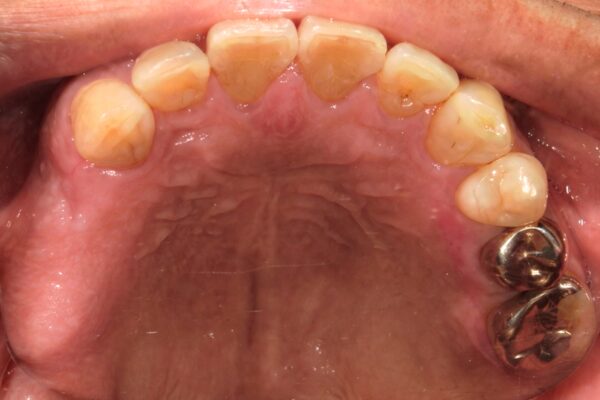

Images